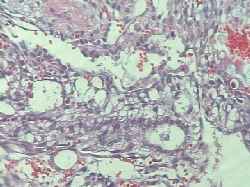

Imagen 3: Mucosa de tipo gástrico